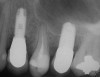

A 55-year-old male was referred for implant placement and prosthetic rehabilitation in the area of tooth No. 15. The tooth had been extracted 4 years prior. The radiograph revealed inadequate bone height for implant positioning (Figure 6). It was decided to insert an implant that was 11.5 mm in length and 3.75 mm in diameter, performing a slight osteotomic maxillary sinus lift. A heterologous bone graft also was planned to obtain a larger sinus lift.

Figure 6  Preoperative radiograph of the area around tooth No. 15.

Figure 6

Figure 7a  Alternating osteotomes with variable conicity used to perform the alveolar remodeling in the area of tooth No. 15.

Figure 7a

Figure 7b  Alternating osteotomes with variable conicity used to perform the alveolar remodeling in the area of tooth No. 15.

Figure 7b